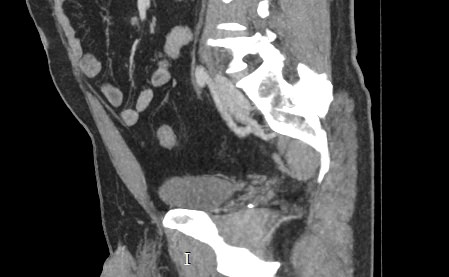

В брюшной полости и забрюшинном пространстве расположены группы лимфатических узлов, которые окружают внутренние органы (желудочные, печеночные, брыжеечные, чревные, подвздошные и др) и располагаются вдоль крупных кровеносных сосудов. Лимфоузлы относятся к периферическим органам иммунной системы человека и выполняют защитную функцию, являясь барьером для проникновения инфекций и задерживают распространение раковых клеток.

Патологические изменения регионарных лимфоузлов часто свидетельствуют о поражении того органа, от которого происходит лимфоотток. Это имеет важное значение для оценки распространенности онкологического процесса, выявления отдаленного метастатического поражения лимфатической системы, а также используется для определения тактики лечения. Кроме того, патология лимфатических узлов может говорить о развитии гемобластозов и лимфопролиферативных заболеваний крови.

Компьютерная томография позволяет детально визуализировать структуру лимфатических узлов, выявить ее неоднородность, гиперплазию, определить деформацию контуров, появление инфильтрации окружающих тканей с образованием пакетов и конгломератов лимфоузлов.

С целью повышения контрастности изображений, выявления патологических изменений в лимфоузлах дополнительно внутривенно вводится рентгеноконтрастное вещество на основе йода. Контраст накапливается в патологических очагах и под воздействием рентгеновских лучей обусловливает их яркое изображение на фоне неизмененной ткани. Контрастирование значительно повышает диагностическую ценность исследования и помогает выявлять многие серьезные заболевания на начальных этапах.

Что показывает КТ лимфоузлов с контрастом

• гиперплазия,

• неоднородность,

• пакеты, конгломераты лимфоузлов,

• изменения контуров,

• инфильтрация окружающих тканей,

• жировая ткань ворот узла,

• сдавление прилежащих органов, сосудов.

• уплотнение клетчатки, наличие жидкости.

• новообразование